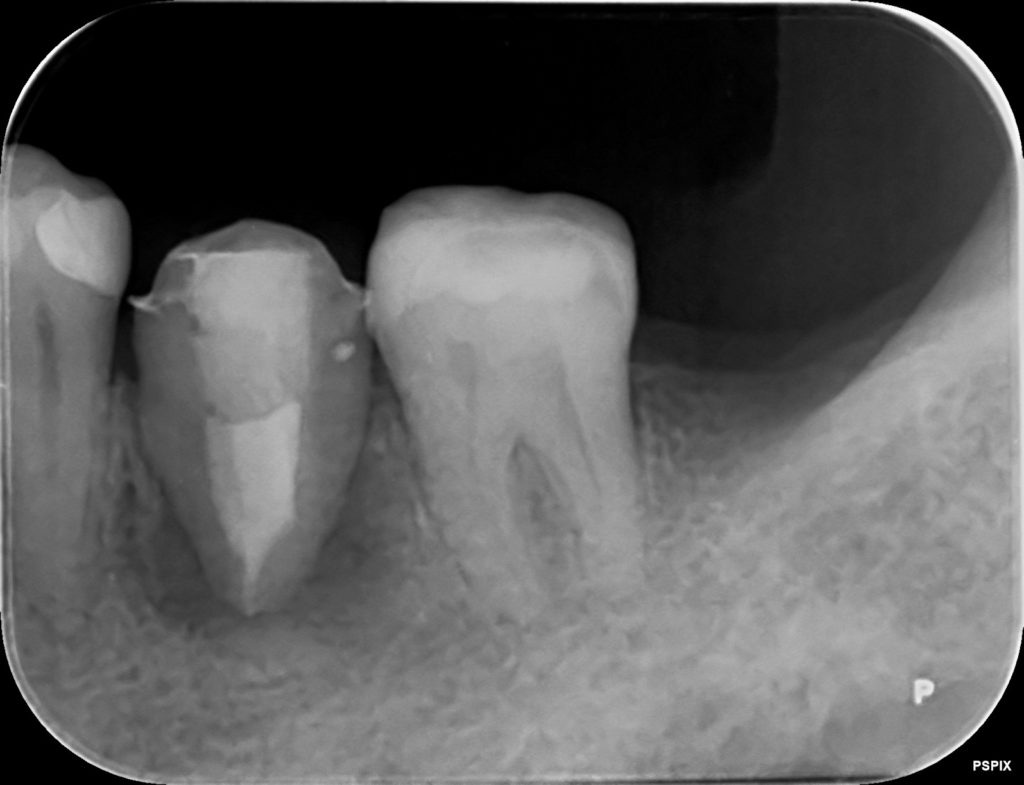

歯の根っこに黒い像レントゲン

赤い丸の、左下6番目の歯です。

歯の根っこに黒い像が見えます。今回は保存が難しいので、

左下の移植、3か月後のレントゲン写真です。

まだレントゲンで黒い影はありますが、黒色が薄くなってきています。

お口の中では揺れはなく、しっかりとくっついています。

歯の内部が白くなっているのは、根管治療をして、材料が入っているからです。

移植した歯は神経が死んでしまうために、根管治療を行います。